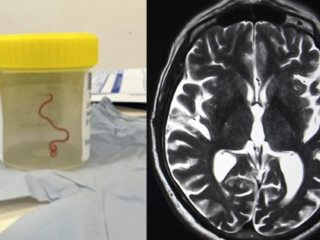

Levende worm uit hersenen van Australische vrouw gehaald